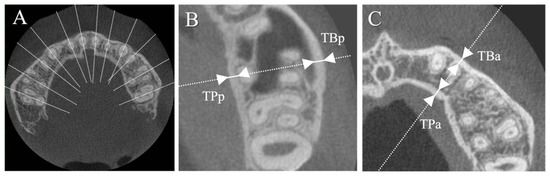

| Da (mm) | 18.67 ± 2.21 | 19.76 ± 2.66 | 0.130 |

| Dp (mm) | 14.12 ± 1.35 | 15.09 ± 1.38 | 0.016 * |

| TBa (mm) | 1.41 ± 0.17 | 1.19 ± 0.13 | <0.001 * |

| TPa (mm) | 1.44 ± 0.32 | 1.25 ± 0.16 | 0.009 * |

| TBp (mm) | 1.44 ± 0.23 | 1.25 ± 0.24 | 0.006 * |

| TPp (mm) | 1.36 ± 0.16 | 1.26 ± 0.20 | 0.055 |